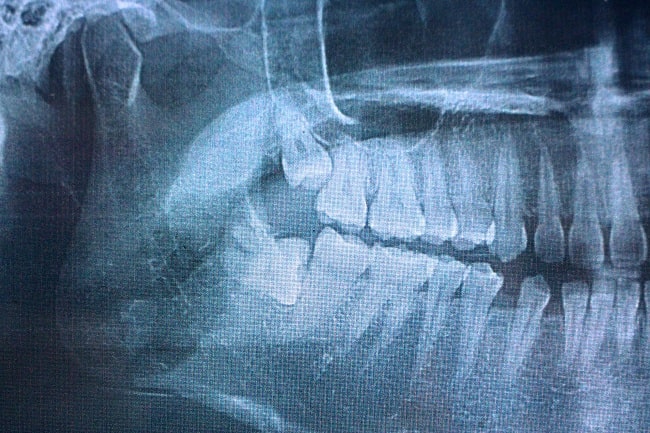

Rontgen gigi panoramik, atau biasa disebut dengan Orthopantomograph (OPG), adalah sebuah prosedur atau teknik pengambilan radiograf pada area maksila dan mandibula yang banyak digunakan misalnya untuk evaluasi gigi impaksi dan penegakan diagnosis kanker rongga mulut. Gambaran yang dihasilkan dari pengambilan teknik radiograf ini adalah dua dimensi, mencakup area telinga kanan hingga telinga kiri, area infraorbital dan bagian bawah mandibula.[1]

Indikasi dari penggunaan prosedur ini adalah untuk melihat gigi impaksi; perawatan orthodonti baik sebelum dan sesudah perawatan; dan penilaian derajat kehilangan struktur tulang dan jaringan periapikal. Rontgen gigi panoramik juga digunakan untuk penentuan penempatan dental implan; menentukan sumber nyeri akibat gigi; penegakan diagnosis anomali pertumbuhan dan perkembangan gigi pada anak serta remaja; hingga penegakan diagnosis kanker rongga mulut.[1,2]